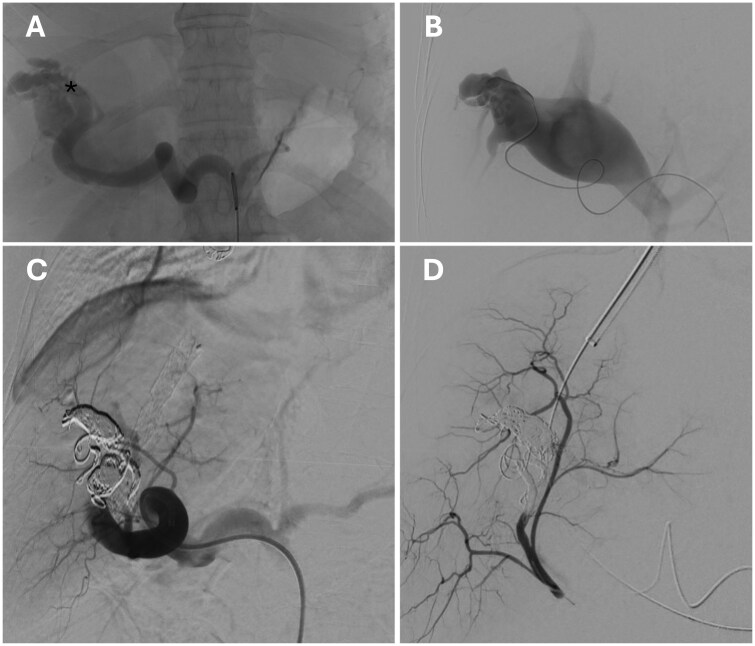

经颈静脉肝内门静脉-全身分流术(TIPS)是治疗门静脉高压(PH)并发症的有效方法。在这里,我们报告了一个复杂的病例,由于胃食管静脉曲张破裂引起的出血性休克,在PH的背景下,最初是由特发性的,可能是先天性的,高流量肝内动脉门静脉瘘(IAPFs)持续,然后是广泛的肠缺血。虽然iapf的闭塞有可能控制内脏动脉血液进入门静脉循环,但它无法控制PH相关出血,因此需要放置补补性TIPS。门静脉压力梯度在IAPFs闭塞后持续显著增加,表明独立的肝内成分导致ph。此外,肝脏组织学显示,长期IAPFs继发于肝实质的窦前/窦前阻塞反应,导致肝内ph的发作。基于这些原因,联合介入方法导致了难愈的门静脉高压出血的解决。避免弥漫性肠梗死的致命性发展。

Transjugular intra-hepatic porto-systemic shunt (TIPS) is a proven strategy for the management of portal hypertension (PH) complications. Here, we report on a complex case of haemorrhagic shock due to the rupture of gastro-oesophageal varices in the context of PH originally sustained by idiopathic, likely congenital, high-flow intrahepatic arterioportal fistulas (IAPFs) preceded by extensive bowel ischaemia. While the occlusion of the IAPFs potentially controlled the steal of arterial splanchnic blood into the portal circulation, it failed to manage PH related bleeding, necessitating the placement of a salvage TIPS. Porta-caval pressure gradient persisted markedly increased after IAPFs occlusion, indicating an independent intra-hepatic component causing PH. Moreover, hepatic histology demonstrated a pre-sinusoidal/sinusoidal barrage response of the hepatic parenchyma secondary to long-standing IAPFs, causing the onset of an intra-hepatic component of PH. For these reasons, the combined interventional approach led to resolution of the refractory portal hypertensive bleeding, avoiding fatal evolution of diffuse bowel infarction.